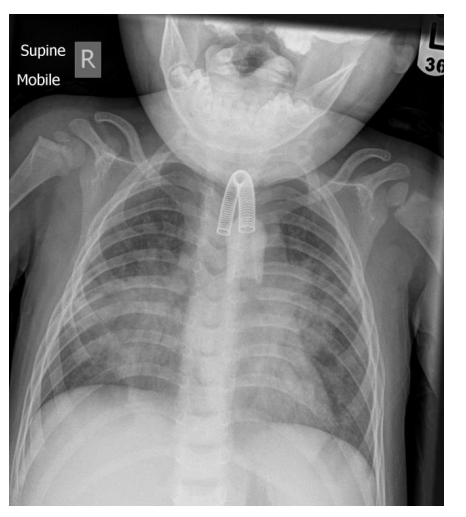

1. Chest X-ray showing SVC stent and tracheostomy tube in situ (Case courtesy of Henry Knipe, Radiopaedia.org, rID: 31410)